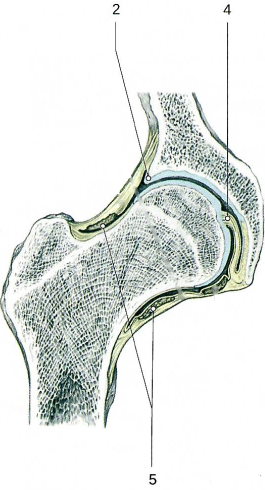

Тазобедренный сустав по строению простой, по форме шаровидный (чашеобразный), по функции многоосный.

Сустав образован полулунной поверхностью вертлужной впадины тазовой кости (имеет вертлужную губу[2]) и головкой бедренной кости.

В суставе возможны сгибание и разгибание, отведение и приведение, пронация и супинация, круговые движения бедра.

Связки, укрепляющие тазобедренный сустав.